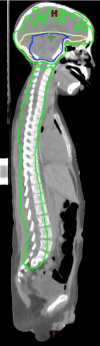

A nine-year-old male patient with a history of diffuse intrinsic pontine glioma (DIPG) presented with an episode of acute neurological deterioration approximately 18 months following completion of a primary course of radiation therapy to the brainstem for DIPG. His symptoms at that time included weakness in the lower extremities, urinary incontinence, and respiratory failure. Magnetic resonance imaging of the brain, cervical, thoracic, and lumbar spine revealed progression of the disease with metastatic deposits involving the craniospinal axis. He subsequently underwent a course of salvage radiation therapy to the craniospinal axis. This case highlights a rare but severe manifestation of metastatic DIPG with spinal involvement.